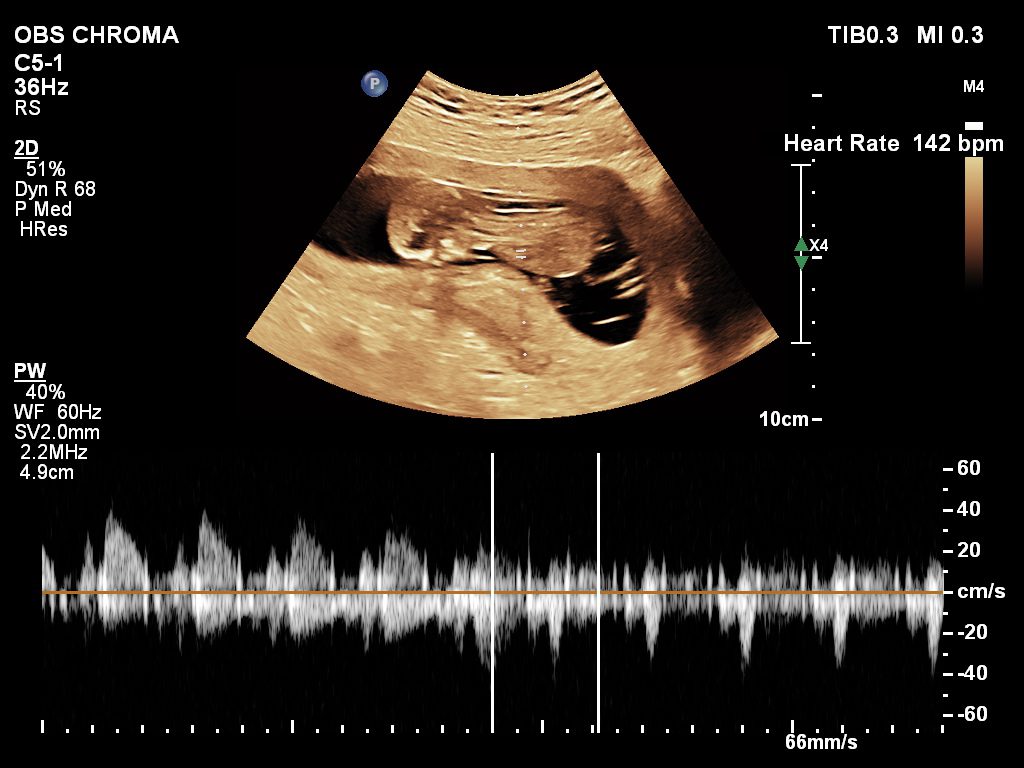

🔹 Fetal Echo / Adult Echo (Echocardiography)

Echo (Echocardiography) is a specialized ultrasound used to examine the heart. Fetal Echo evaluates the baby’s heart structure and function during pregnancy, while Adult Echo checks heart health in adults. It helps detect congenital heart defects, valve problems, and blood flow issues. If you need a fetal echo in Kathmandu, this test plays a vital role in early diagnosis and treatment planning.